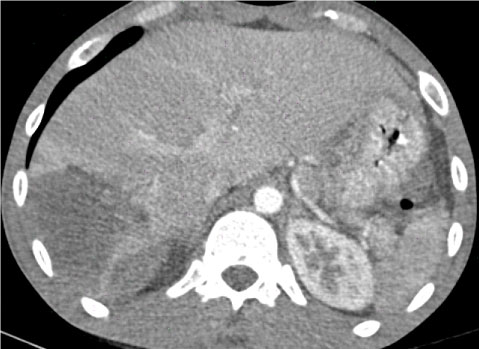

A 25-year-old male was transferred to the Emergency Department of the tertiary Regional Hospital of Nikea after a high-energy motor-vehicle collision. Initial management was based on the protocols of Advanced Trauma Life Support (ATLS). At first evaluation, he was haemodynamically unstable with sinus tachycardia and 80 mmΗg systolic blood pressure requiring bolus infusion. The patient responded rapidly to the infusion of 1 lt of Ringer's solution and his hemodynamic condition stabilized having a heart rate of 90 and 80 mmHg mean arterial pressure. At physical exam, he had a mild left upper quadrant abdominal pain without signs of peritonitis and mild pelvic tenderness without instability. His airway, lungs and brain presented no clinical radiological damage, GCS 14/15. Further evaluation for injuries showed a complete displaced right femoral shaft fracture causing deformity. Inline longitudinal traction was applied, realigning the extremity and maintaining limb perfusion. He reported no significant past medical history and denied any medication. A FAST scan was carried out that showed perisplenic and perihepatic fluid. Since he remained stable, a multi-detector whole-body contrast-enhanced computed tomography was performed revealing an American Association for the Surgery of Trauma (AAST) grade II splenic injury (Figure 1), a AAST grade II liver injury (Figure 1) and a non-displayed fracture of right ischiopubic ramus with the active contrast extravasation indicating arterial bleeding (Figure 2).

Figure 1: The contrast computed tomography (CT) scan demonstrates a large parenchymal hematoma in segment 6 and 7 of the liver with no active extravasation and an intraparenchymal hematoma of the spleen. View Figure 1